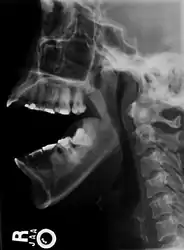

As with other joint dislocations, clinical history and examination are important for diagnosis. Commonly, plain and panoramic X-rays are used to determine the relative position of the mandibular condyle. If a complex or unusual injury is suspected, computed tomography is most reliable in diagnosing dislocation and possibly associated fractures or soft tissue injuries.

Bilateral anterior dislocation of the jaw

Jaw dislocation following relocation

CT image demonstrating jaw dislocation